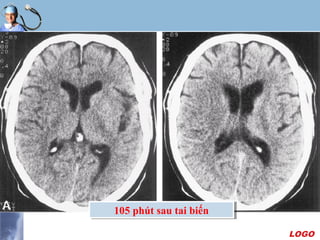

105 phút sau tai biến105 phút sau tai biến

Xác định thời gian nhồi máu

 Phân biệt nhồi máu mới và cũ

- Giảm đậm độ ít : vài giờ

- Giảm đậm độ dễ nhận thấy : vài ngày